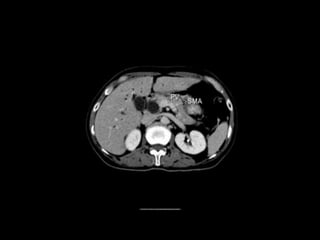

Cross section anatomy of abdominal ct scan

Cross section anatomyof abdominal ct scan